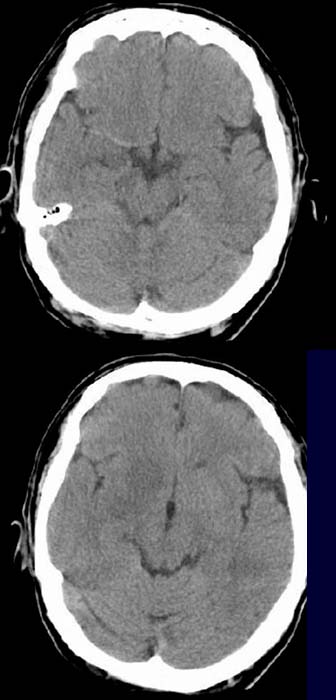

Patient, 57 Jahre alt, mit Halbseitenlähmung links.

CCT nativ (ohne Kontrastmittel).

Hyperdense

Darstellung der A.

cerebri media. Hypodense Darstellung und verminderte Abgrenzbarkeit der Stammganglien

rechts. Leichte

Konturunschärfe der Rindenmarkgrenze rechtsim Mediastromgebiet.

Hyperdenses

Media-Zeichen rechts als Hinweis aufeinen frischen

Thrombus.

Frischer Mediainfarkt rechts (<12h) mit leichter ödematöser

Schwellung.